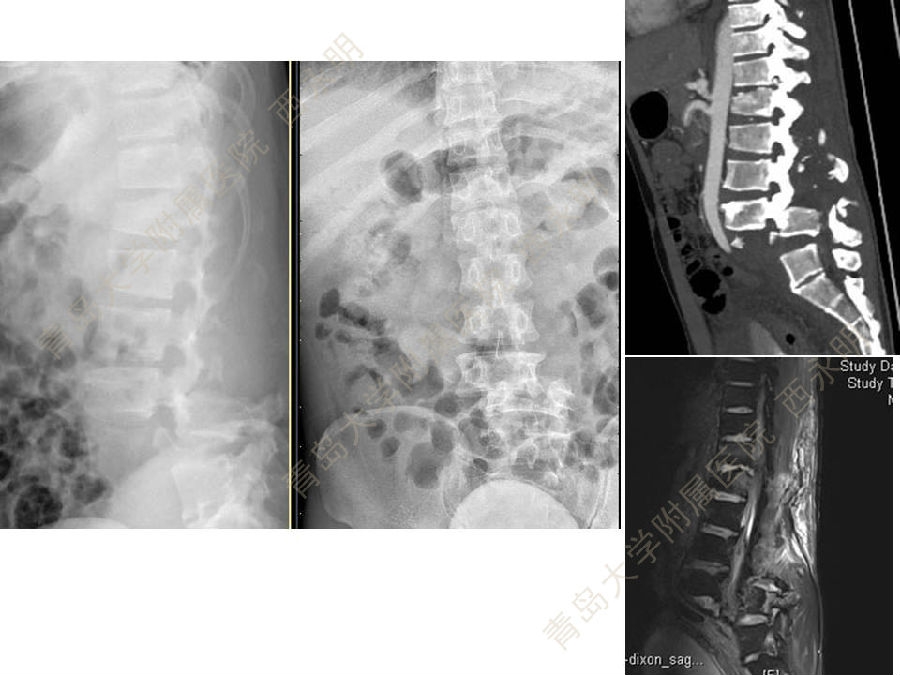

皮质骨螺钉技术及临床应用

颈椎伤病、脊柱畸形和脊柱肿瘤以及颈胸腰椎退变性疾病的微创治疗。长期从事临床一线的医、教、研工作,在多年的临床实践中积累了丰富的经验,并形成了以脊柱外科为专业方向,以颈椎外科、脊柱畸形和脊柱肿瘤为专业特色。